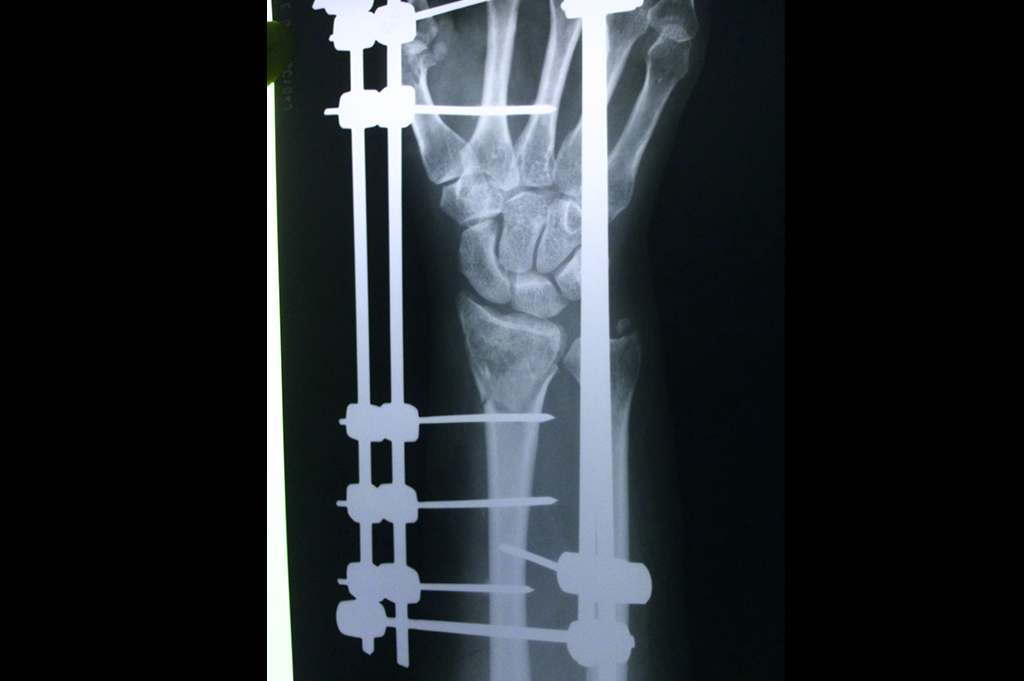

Lower Radius